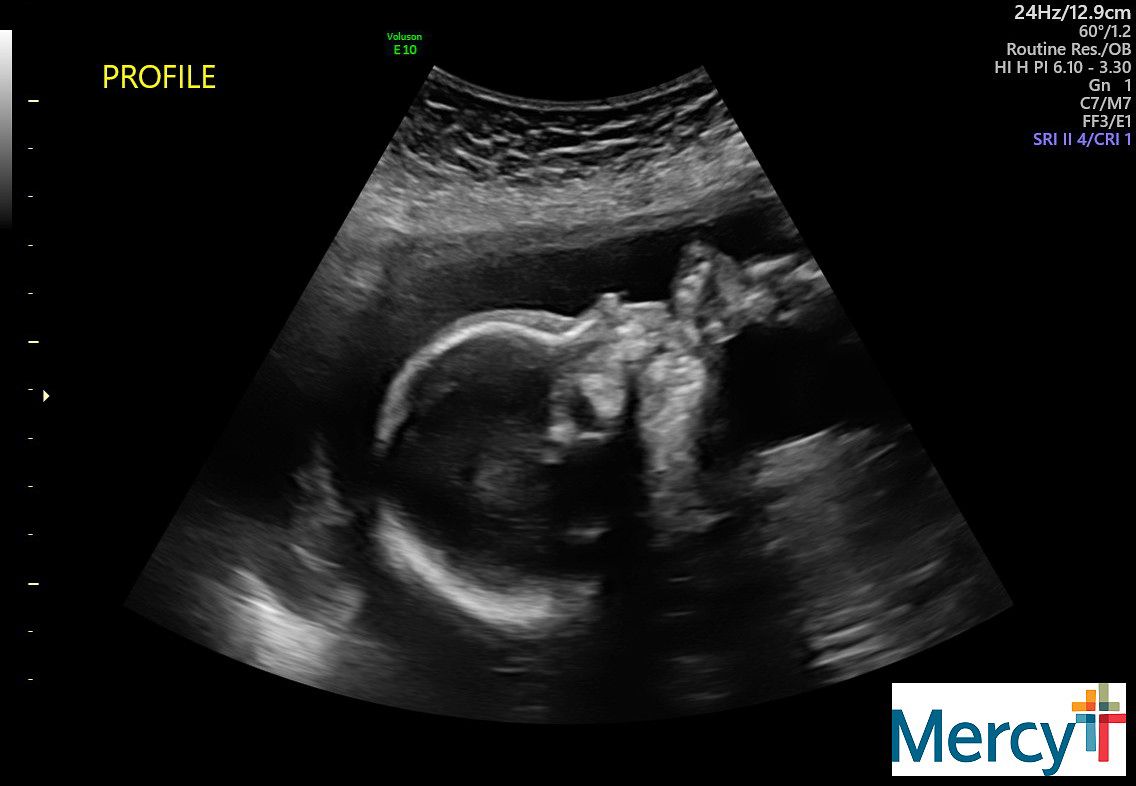

Sydney has her weekly doctor appointment this morning for the baby. Mitzi is grateful she can be there and support. Baby Benson, looking good already!